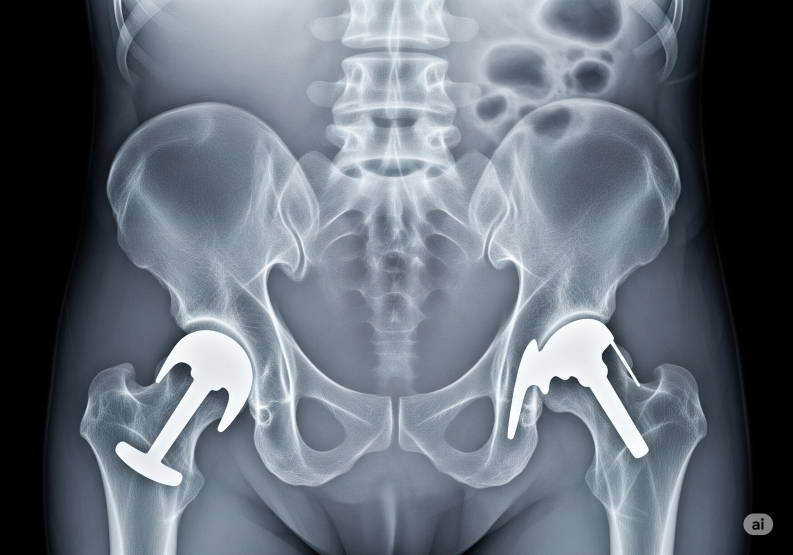

Hip replacement (also called hip arthroplasty) is a surgical procedure where a damaged hip joint is replaced with an artificial implant (prosthesis).

1.Total Hip Replacement (THR)

. Both the acetabulum (hip socket) and the femoral head (ball part of thigh bone) are replaced.

. Most common type.

2.Partial Hip Replacement (Hemiarthroplasty)

. Only the femoral head (ball) is replaced.